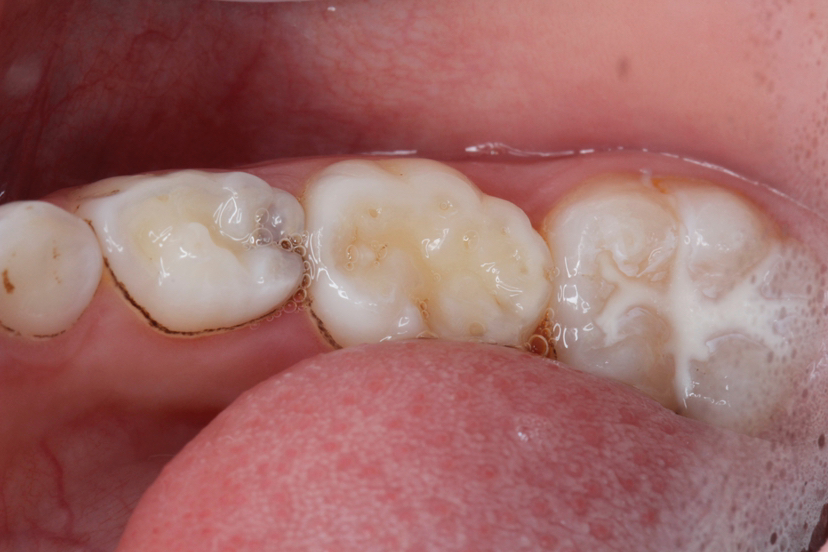

牙齿的咬合面布满了深浅不一的窝沟,这些细小的缝隙最容易藏匿食物残渣和细菌。儿童由于刷牙技巧不够熟练,很难彻底清洁这些部位。窝沟封闭技术就是将一种特殊的树脂材料涂布在牙齿表面,形成一层保护膜,将窝沟封闭起来,阻止细菌和食物残渣的侵入。

窝沟封闭的最佳时机是在恒磨牙萌出后尽快进行,一般在6-8岁和11-13岁这两个阶段。这时新长出的恒牙还没有受到细菌侵蚀,及时进行封闭能获得最佳效果。